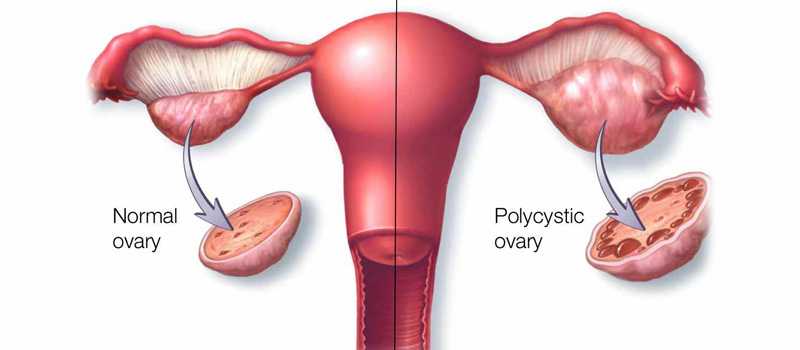

Polycystic ovary syndrome (PCOS) is a health problem that affects one in 10 women of childbearing age. Women with PCOS have a hormonal imbalance and metabolism problems that may affect their overall health and appearance. PCOS is also a common and treatable cause of infertility.

Polycystic ovary syndrome (PCOS), is a common health problem caused by an imbalance of reproductive hormones which creates problems in the ovaries. The ovaries make the egg that is released each month as part of a healthy menstrual cycle. With PCOS, the egg may not develop as it should or it may not be released during ovulation as it should be.

PCOS can cause missed or irregular menstrual periods. Irregular periods can lead to:

• Infertility (inability to get pregnant). In fact, PCOS is one of the most common causes of female infertility.

• Development of cysts (small fluid-filled sacs) in the ovaries.

• Polycystic ovarian syndrome – the ovaries develop clusters of blister-like cysts. Symptoms include irregular periods and excessive hair growth. Women with polycystic ovarian syndrome are especially prone to amenorrhoea when they gain weight.